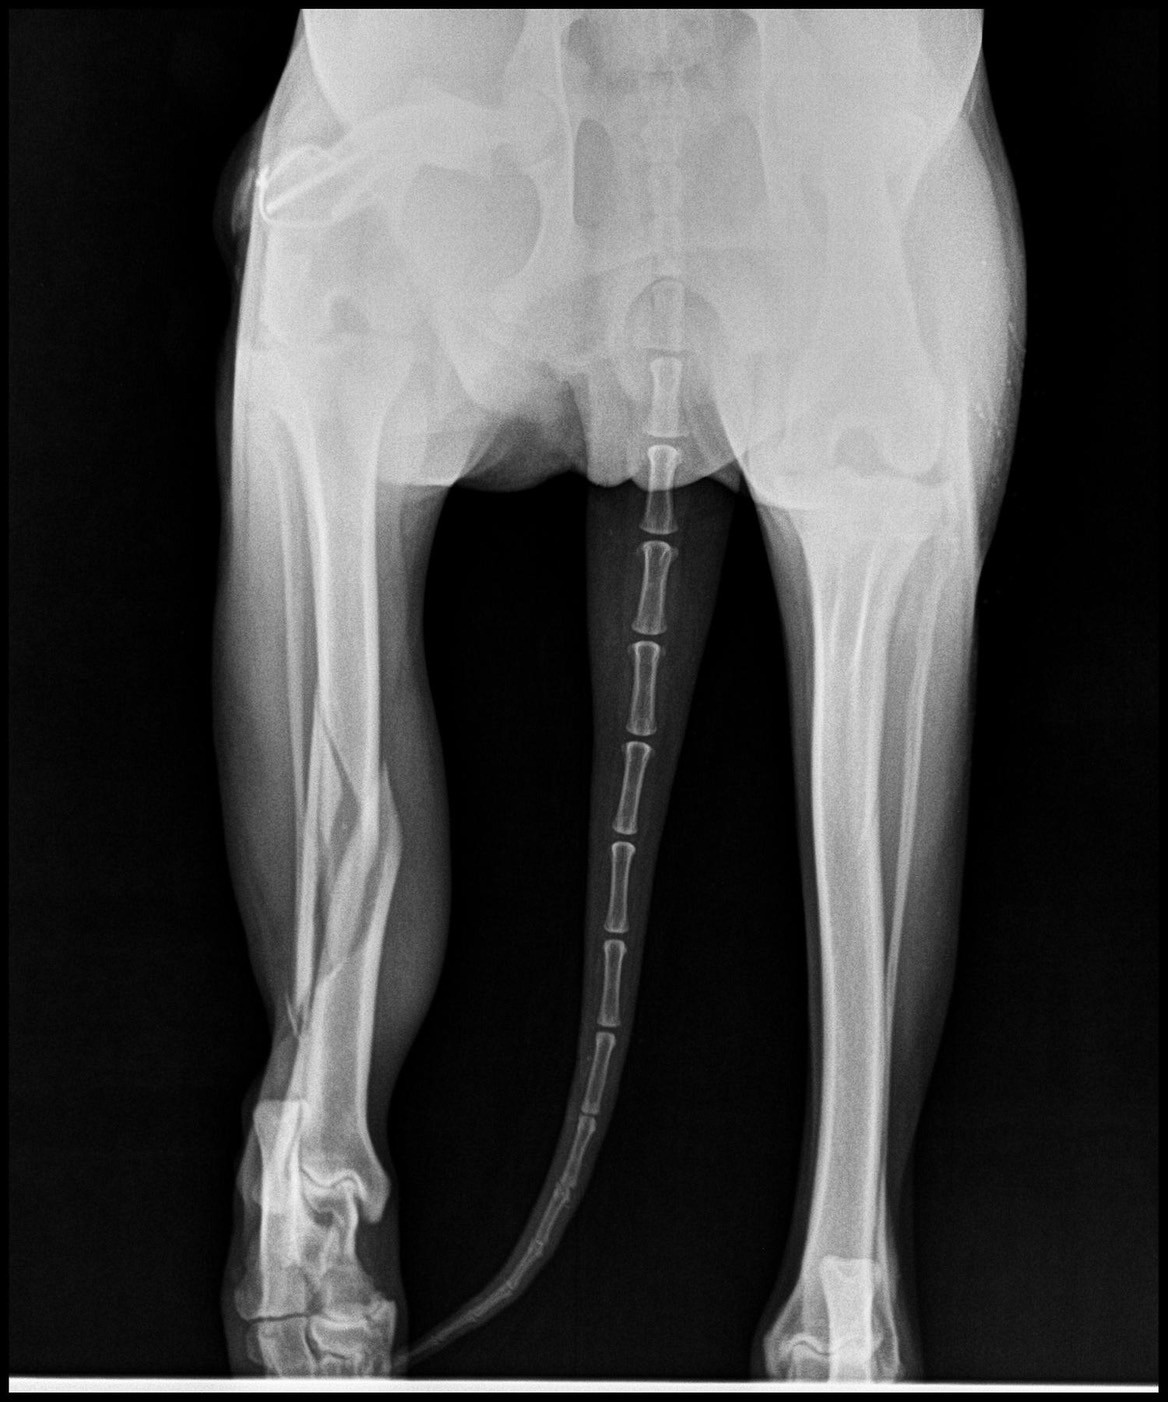

น้องปอม” สุนัขพันธุ์ไทยน้ำหนัก 27 กิโลกรัม ถูกนำตัวเข้ารับการตรวจรักษาที่โรงพยาบาลสัตว์ วิทยาลัยสัตวแพทยศาสตร์อัครราชกุมารี มหาวิทยาลัยวลัยลักษณ์ หลังประสบอุบัติเหตุถูกรถชน ทีมสัตวแพทย์ได้ทำการ เอกซเรย์ (X-ray) พบว่า กระดูกหน้าแข้งข้างขวา (right tibia) ของน้องปอม หักแบบเกลียวบริเวณกลางกระดูก (Spiral fracture at midshaft of right tibia) ซึ่งเป็นการแตกหักจากแรงบิดที่ทำให้กระดูกแตกเป็นแนวเกลียว